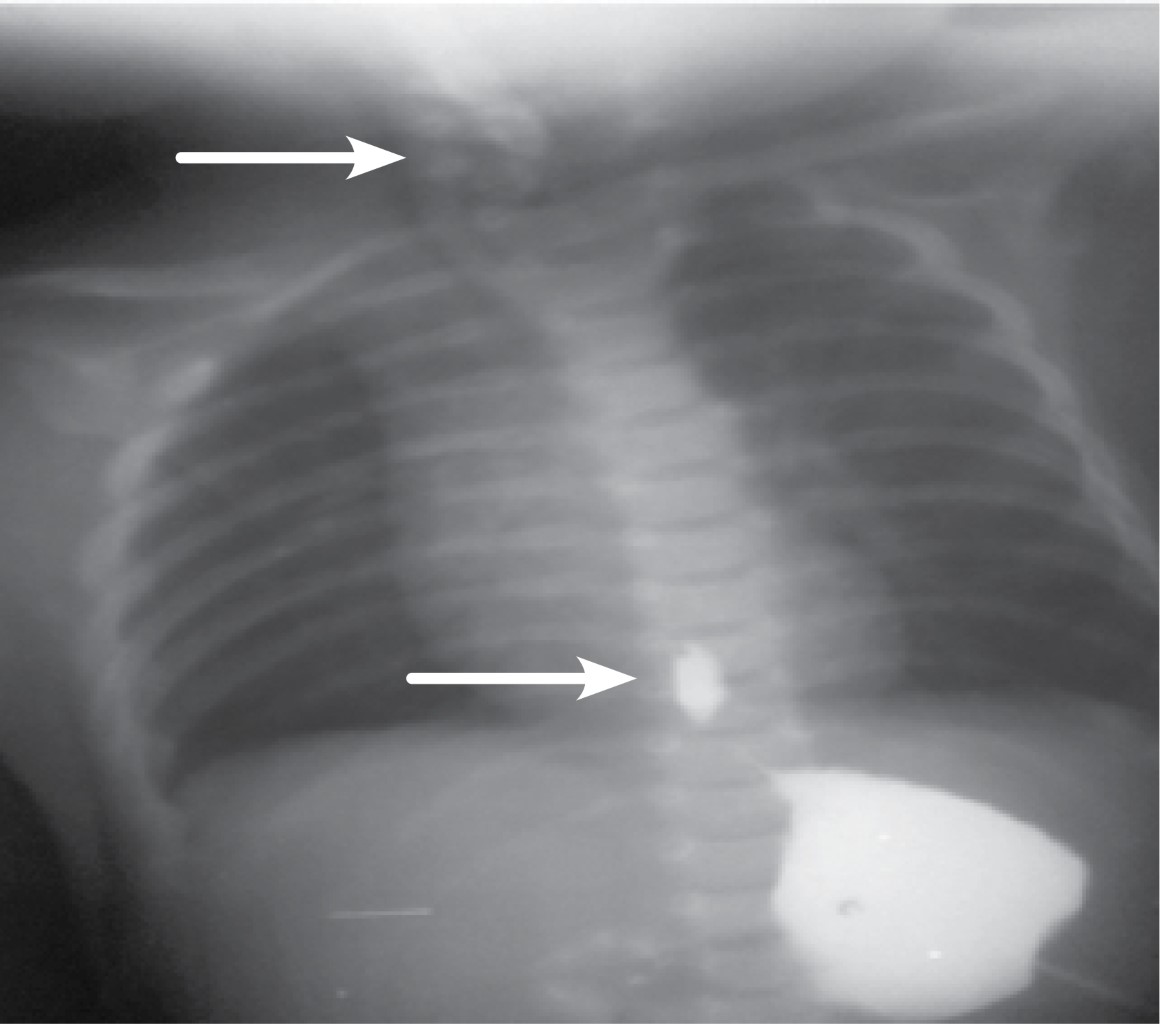

Se realiza gastrostomía Stamm modificada al segundo día de vida, a través de ella se hace estudio contrastado, se encuentra cabo distal en onceava vértebra torácica (intraabdominal), se coloca sonda radiopaca en cabo proximal localizándose dicho segmento a nivel de sexta vértebra cervical, con una distancia inicial de cabos de 12 vértebras (ningún segmento esofágico dentro de tórax). Se mantiene seis semanas sin esofagostomía, con sonda doble lumen de aspiración e irrigación para control de secreciones y con alimentación enteral por sonda de gastrostomía, en este momento se repite el estudio contrastado, en el cual se visualiza cabo proximal en C-7 y distal en T-10 (Figura 2), ya dentro de tórax (hubo ganancia de tres cuerpos vertebrales con respecto al inicio).

Con este avance se realiza toracotomía posterolateral derecha, con abordaje extrapleural, disecando ambos cabos esofágicos (incluyendo disección hiatal de cabo inferior) y colocando jaretas de seda, las cuales se exteriorizan para una elongación esofágica tipo Foker (Figuras 3 y 4), con tracciones seriadas cada 24 horas y controles radiográficos diarios en los que se permite visualizar la aproximación de los marcadores radiopacos colocados en ambos cabos (Figura 5).

Figura 2